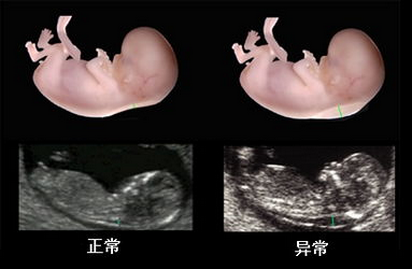

在线咨询系统彩超和四维彩超我们都不陌生,尤其是孕妇,在怀孕期间孕妈妈一定有做过类似的检查,此二者都是观察胎儿健康的检查项目,所以在产检中非常重要,那么,系统彩超和四维彩超有什么区别呢?下面就让贵阳和谐阳光产科医生为我们解答。

1.四维彩超:由于四维彩超是一种立体B超检查,所以除了能检查常规的项目之外,还可针对心肝脾肺各个脏器 及唇腭裂方面的筛查。

2.系统彩超:系统彩超早期的时候可以通过颈后透明层排除宝宝智力以及先天愚型。对胎体发育的健康状况进行比较准确的评估。

对胎儿全面排畸,孕妈妈除了需要做系统彩超以外,还需要做四维彩超。因为,系统彩超仅仅是对胎儿先天愚型和智力缺陷等进行排查。四维彩超是对胎儿面部、颜色等体表器官进行筛查。因此,贵阳妇产医院产科医生建议,全面排畸系统彩超和四维彩超都要做。